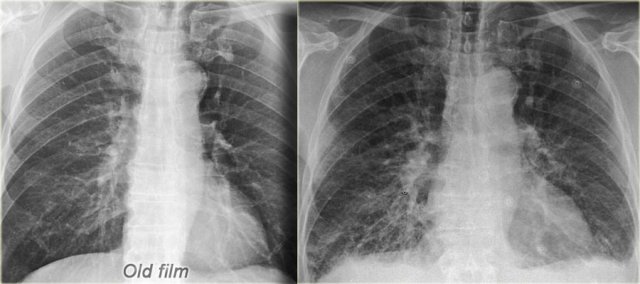

Old film for comparison (left) CHF with redistribution, interstitial edema and some pleural fluid Old film for comparison (left) CHF with redistribution, interstitial edema and some pleural fluid

The cardiothoracic ratio (CTR) is the ratio of the transverse diameter of the heart to the internal diameter of the chest at its widest point just above the dome of the diaphragm as measured on a PA chest film.

An increased cardiac silhouette is almost always the result of cardiomegaly, but occasionally it is due to pericardial effusion or even fat deposition.

The heart size is considered too large when the CTR is > 50% on a PA chest x-ray.

A CTR of > 50% has a sensitivity of 50% for CHF and a specificity of 75-80%.

An increase in left ventricular volume of at least 66% is necessary before it is noticeable on a chest x-ray.

On the left a patient with CHF.

There is an increase in heart size compared to the old film.

Other signs of CHF are visible, such as redistribution of pulmonary flow, interstitial edema and some pleural fluid.